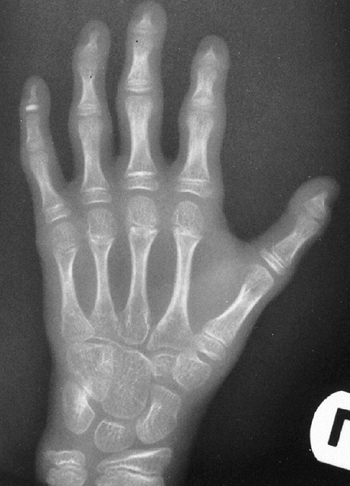

Arachnodactyly is defined, for purposes of radiographic readings, as an

increase in the ratio of length to width of the second to fifth

metacarpals (Fig. 9.2). The average ratio of

the lengths of the second to fifth metacarpals, divided by the widths

of the respective diaphyses, is greater than 8.8 in male patients and

greater than 9.4 in female patients with Marfan syndrome (21).

Figure 9.2 Hands showing arachnodactyly. Notice the long, thin metacarpals and phalanges.